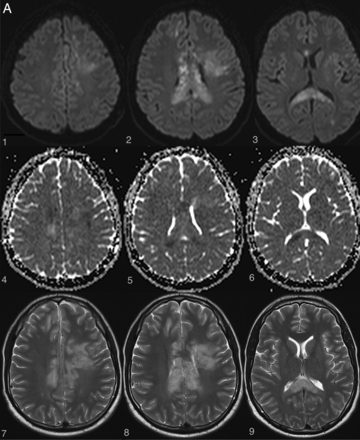

Examples of irreversible brain and spinal cord lesions due to decompression sickness (A, B, and C are taken from the same patient). A, On DWI (1, 2, 3, 4, 5, 6), the areas of restricted diffusion correspond to lesions of the corpus callosum and frontal white matter on both sides. They appear as high signal on T2WI (7, 8, 9). B, Sagittal (1 and 2, white arrows) and axial (3 and 4, white arrows) T2WI shows a cervicothoracic (C7–T1) lesion appearing as high signal without contrast enhancement on T1WI (2). C, On follow-up 1 month later, the lesions described in A and B are still present on these brain (1, 2, 3, 4) and spine (5, 6) images. Note the enhancement of the corpus callosum (3 and 4). Lesions of the right frontal deep white matter and corpus callosum have healed and now appear as “little cavities.” Similar features are usually seen in ischemic or necrotic lesions of the central nervous system.

The exact mechanism through which nitrogen bubbles cause brain and spine damage is still highly debated, and there are currently 3 theories supporting 3 different pathophysiologic mechanisms: arterial occlusion, venous infarction, and in situ nitrogen toxicity. The following support the arterial occlusion theory: 1) the predominance of cerebral lesions in arterial gas embolisms with usually a clinical and radiologic stroke-like presentation (restricted diffusion appearing as hyperintensity on DWI with low values on the ADC map, high signal on T2WI, and usually no contrast enhancement) (Fig 3A).7,21,22 2) The finding that nitrogen bubbles can interrupt arterial blood supply to the brain and spine either by direct obstruction of small capillaries or by activation of pathologic clotting at the blood-bubble interface.23⇓⇓–26 This effect on clotting is increased in case of low hematocrit, explaining the higher risk of severe cardiopulmonary and neurologic decompression sickness in dehydrated divers.27⇓⇓–30 3) The higher prevalence of a patent foramen ovale in patients experiencing decompression illness31⇓⇓⇓⇓⇓⇓⇓–39 could favor paradoxic embolization of either nitrogen bubbles or pathologically formed thrombi with subsequent ischemic infarcts in the brain40 or spine, where the collateral circulation network is less robust.41 4) The presence of extensive gray matter lesions in some neurologic decompression sickness cases—gray matter lesions being typically seen in arterial infarction processes.11,18,42 5) Hypoperfused areas compatible with embolic cerebral arterial occlusion are observed in some patients with decompression illness when using SPECT with hexamethylpropyleneamine oxime (HMPAO) marked with a metastable nuclear isomer of the radioisotope technetium Tc99m (the product is sometimes referred to as exametazime).43,44

On the other hand, various radiologic and histopathologic findings have been published to support the venous infarction theory. First, the more frequent occurrence of lateral and posterior column white matter lesions compared with gray matter lesions in spinal cord decompression sickness is more likely a consequence of an obstruction of the slow-flowing epidural venous bed by nitrogen bubbles, which leads to vasogenic edema (Figs 1 and 2).5,8 In some cases, there may be additional venous infarction (Fig 3B, -C). Similar lesions have been provoked experimentally in dogs.9 Second, several histopathologic studies have demonstrated venous obstruction and white matter congestion.45,46 Third, vasogenic edema, appearing as high signal on both DWI and ADC maps, was observed by Vollmann et al in 201147 in a case of spinal cord decompression sickness, also suggesting a venous rather than arterial pathologic process.